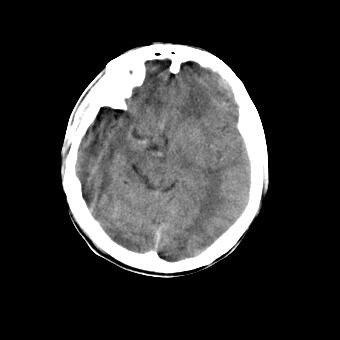

标题: CT16478:男 头晕 恶心 呕吐 [打印本页]

标题: CT16478:男 头晕 恶心 呕吐

病人不合作,图像质量差,右额叶及后纵裂可见高密度影,建议复查。

脑水肿?建议短期复查。

图像不好看,暂时考虑脑水肿,稳当起见建议复查

弥漫性脑肿胀,建议增强检查

脑水肿?建议短期复查

[quote]以下是引用叶子123在2008-11-13 9:55:00的发言:[br]患者因煤气中毒入院,临床及ct均诊断一氧化碳中毒性脑病[br][br]

没有提供病史,图像质量又差,很难做诊断。